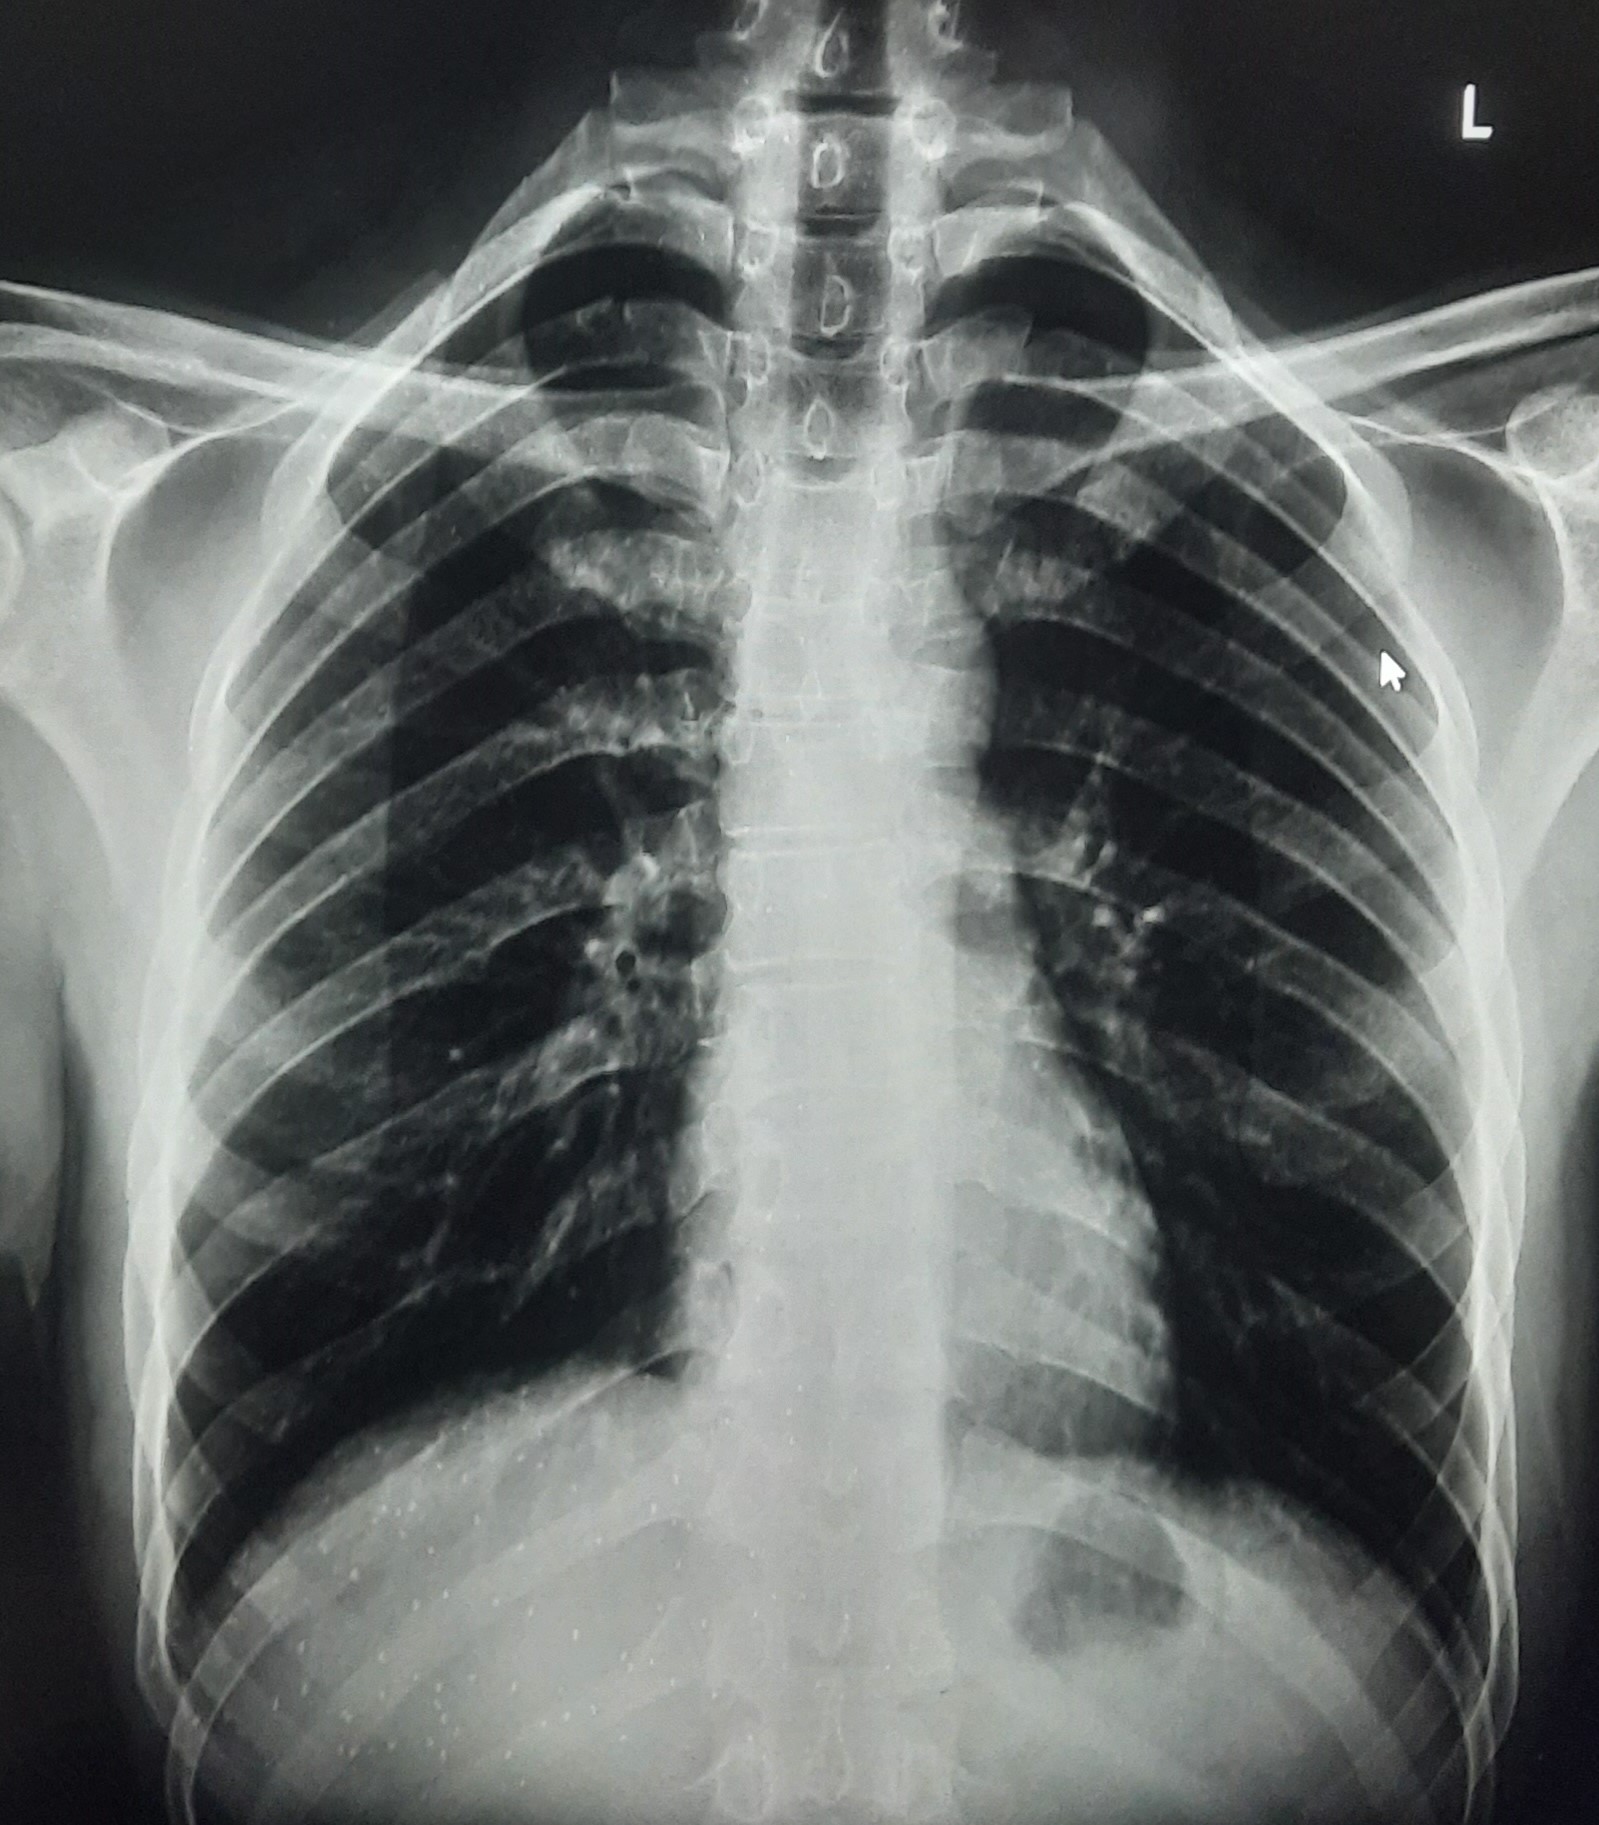

| 332 | IGGMC, Nagpur, Nagpur | P2 | 29-4140 | Mohamad Bashir | Consent taken on Paper | 75 Yrs. |

Provisional Diag : COPD

Final Diag : COPD In intense exerbation |

Non-TB Case (Confirmed) | COPD changes seen | Abnormality visible on x-ray |